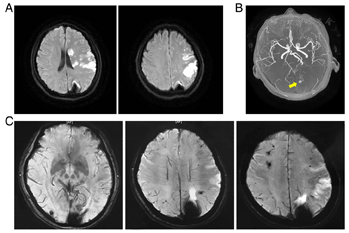

Supportive treatment and intensive monitoring was initiated for her, and she did not deteriorate. The Susceptibility Weighted Imaging (SWI) revealed numerous hypointense foci, in addition to the first known lesions, mimicking CAs in the brain and indicating previous hemorrhages (Fig. 2). Additional DWI detected multiple minor acute infarction throughout the left hemisphere, including left basal ganglia, thalamus and cortex (Fig. 2).

To identify the cause of embolism, a MR angiography and echocardiogram was performed. No abnormalities were detected in the large intracranial arteries by MR angiography, but a suspicious small aneurysm next to one of the CA like lesions (Fig. 2). Echocardiogram demonstrated a 55*28 mm left atrial myxoma, blocking blood flow through the mitral valve. After several days of conservative treatment and rehabilitation, she was able to speak slowly and the muscle strength of the right limb improved to Grade 4.